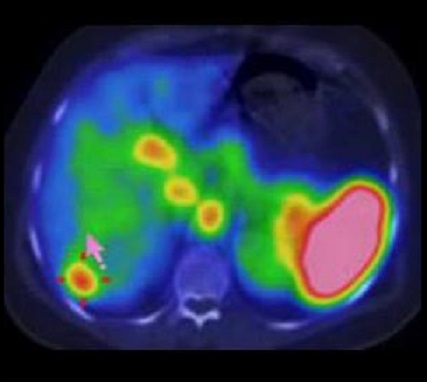

Image radiologique TDM et image de PET/CT des

adenocarcinomae du colon en extension localise et extension

metastasique :